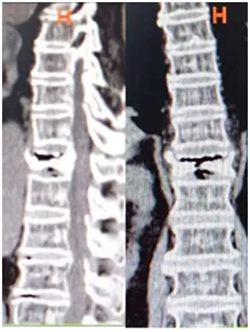

▲ 术前CT